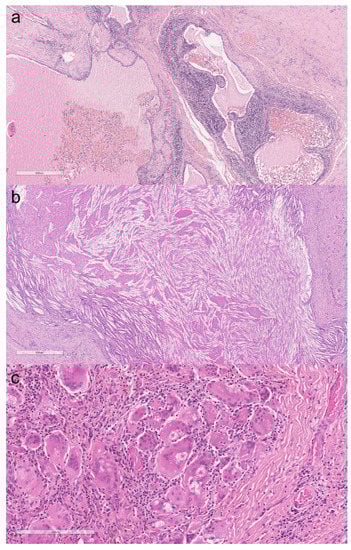

3.1. Thymic Cysts

3.2. Thymic Carcinoma

4.1. Thymic Cysts

4.2. Thymic Carcinoma